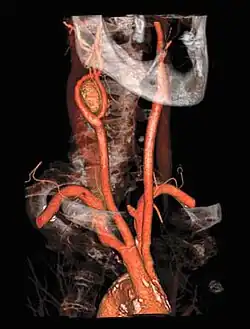

Volume Rendered Carotid Angiogram

This method of imaging is used primarily to produce images of arteries, such as the aorta, pulmonary artery, cerebral, carotid and hepatic arteries.

CT angiography is a contrast CT taken at the location and corresponding phase of the blood vessels of interest, in order to detect vascular diseases. For example, an abdominal aortic angiography is taken in the arterial phase in the abdominal level, and is useful to detect for example aortic dissection.[10]